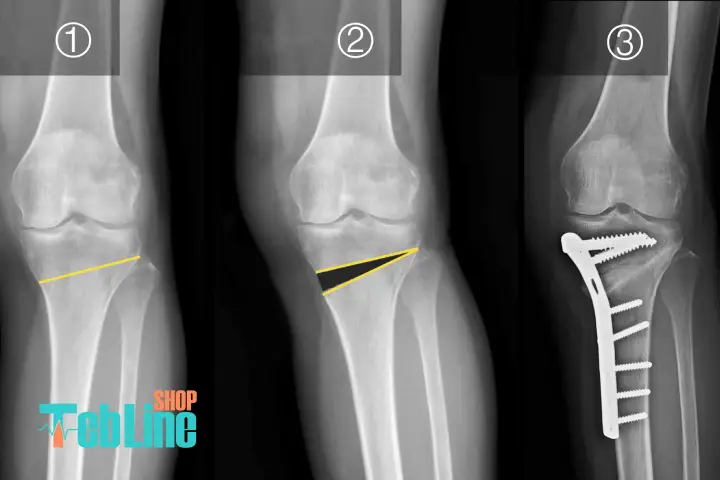

جراحی استئوتومی زانو نوعی عمل ارتوپدی است که با هدف اصلاح محور استخوانها و کاهش فشار وارد شده بر بخشی از مفصل زانو انجام میشود. در این روش، جراح با برش و تغییر زاویه استخوان ران یا ساق پا، تعادل جدیدی در مفصل ایجاد میکند تا وزن بدن به صورت یکنواختتری توزیع شود.

برش استخوان: جراح بخشی از استخوان ران یا ساق پا را برش میدهد تا زاویه آن تغییر کند.

اصلاح محور زانو: زاویه استخوان به گونهای تغییر داده میشود که فشار به طور متوازنتری روی مفصل پخش شود.

فیکس کردن استخوان: با استفاده از پلاکها، پیچها یا صفحات مخصوص استخوان در جای اصلاحشده ثابت میگردد.